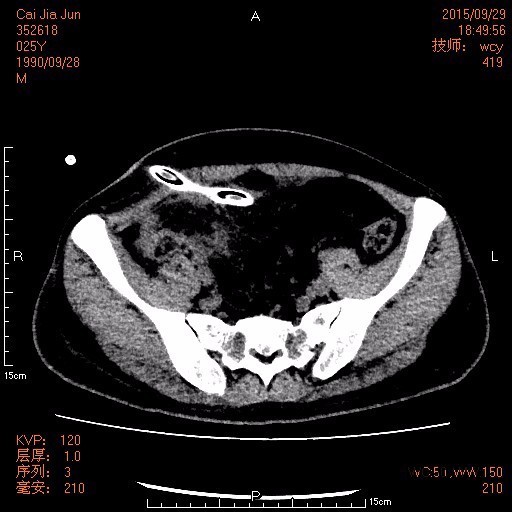

25岁男性患者,因阑尾穿孔引流术后10天收住入院。2周前无明显诱因出现右下腹痛,伴发热、恶心、呕吐,最高体温达39℃,在当地医院行抗感染、补液等处理后无明显好转,于2015-09-17在全麻下行腹腔镜下阑尾周围脓肿及盆腔脓肿引流置管术。2015-09-26行介入置管引流术,引流出大量灰黄色脓液伴恶臭。遂自行出院来我院就诊。

查体: 腹部平软,右下腹及右上腹可见两条引流管,引流出棕色臭味脓液,右下腹有压痛、反跳痛,余腹无压痛及反跳痛。 辅查: 1.腹部CT:1.原阑尾炎穿孔并周围及腹盆腔多发包裹性脓肿形成治疗后复查,现累及范围如上述,与前对比盆腹腔多发脓肿明显吸收变小。 2.腹膜炎;腹腔少量积液,与前对比减少。 3.双侧胸腔积液,与前对比减少;双肺下叶节段性肺不张,较前复张。 4.肝多发小囊肿。 2.胸片:1.右侧胸腔中量积液,左侧胸腔少量积液。 2.双下肺炎症及肺压缩性不张。 3.腹腔引流液培养:大肠埃希菌;屎肠球菌(D群)。

诊断:阑尾穿孔并腹腔脓肿形成。 治疗:伤口换药、抗感染、补白蛋白、控制血糖等处理,复查CT见腹腔包裹性脓肿明显吸收变小,予拔除引流管,无明显发热,予办理出院。